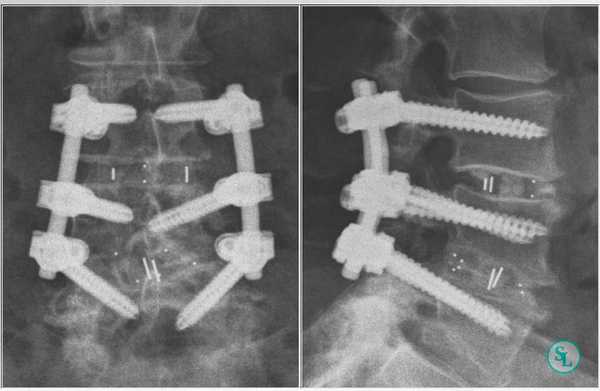

В подавляющем большинстве случаев операции на поясничном отделе позвоночника выполняются задним доступом с выбором межтелового способа фиксации позвонков. Вмешательство через передний доступ осуществляют исключительно в сложных клинических случаях и при оскольчатых переломах.

Существует несколько способов проведения межтелового спондилодеза поясничного отдела:

- передний (ALIF);

- задний(PLIF);

- трансфораминальный(TLIF).

Чтобы иммобилизация позвоночно-двигательного сегмента была максимально надежной, нередко операция дополняется выполнением транспедикулярной фиксации. В таком случае устанавливаются специальные металлические конструкции, которые еще более упрочняют скрепление тел позвонков.

Транспедикулярная фиксация или ТПФ - операция, при которой позвонки фиксируются и стабилизируются при помощи специальных имплантов (транспедикулярных винтов). В каждом позвонке есть точка ввода винта, которую установил в 1985 году Рой Камилл — это точка пересечения поперечного отростка позвонка с верхнем суставным отростком. С помощью специальных инструментов в эту точку, вкручиваются винты определяя анатомически правильное расположение позвоночника, тем самым излечивая заболевание. Первые попытки установки имплантов были в 60-70 гг. прошлого века и с тех пор является «золотым стандартом» в лечения переломов и различных заболеваний позвоночника.

Размер закрепляющих винтов для каждого больного подбирается индивидуально. Различают моноаксиальные и полиаксиальные винты, также разработаны варианты с боковой фиксацией стержня. Они вводятся по конвергентной монокортикальной методике, подразумевающей перфорацию позвонка только в точке входа винта.

Винты изготавливаются из титана, что гарантирует их высокую стойкость к различным деформирующим нагрузкам. Они оснащены поверхностными колпаками, обеспечивающими стабильность положения конструкции и ее защиту от перекоса. Все винты установленной системы объединяются специальными пружинистыми металлическими механизмами, что равномерно перераспределяет нагрузку на них.